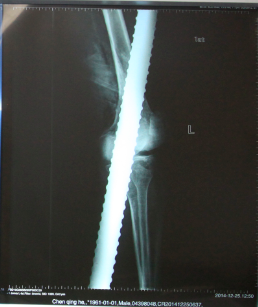

北京积水潭医院急诊的大夫和护士迅速对病人进行抢救,心电监护,开放静脉,并将患者左腿上的裤子小心翼翼的剪开。创伤骨科孙旭大夫和手外科童德迪、薛云浩大夫一边了解病人的情况,一边给病人进行检查,病人左脚没有知觉,怀疑至少有一根神经有损伤,为判断是否有骨折,拍了X光片子。

X光片